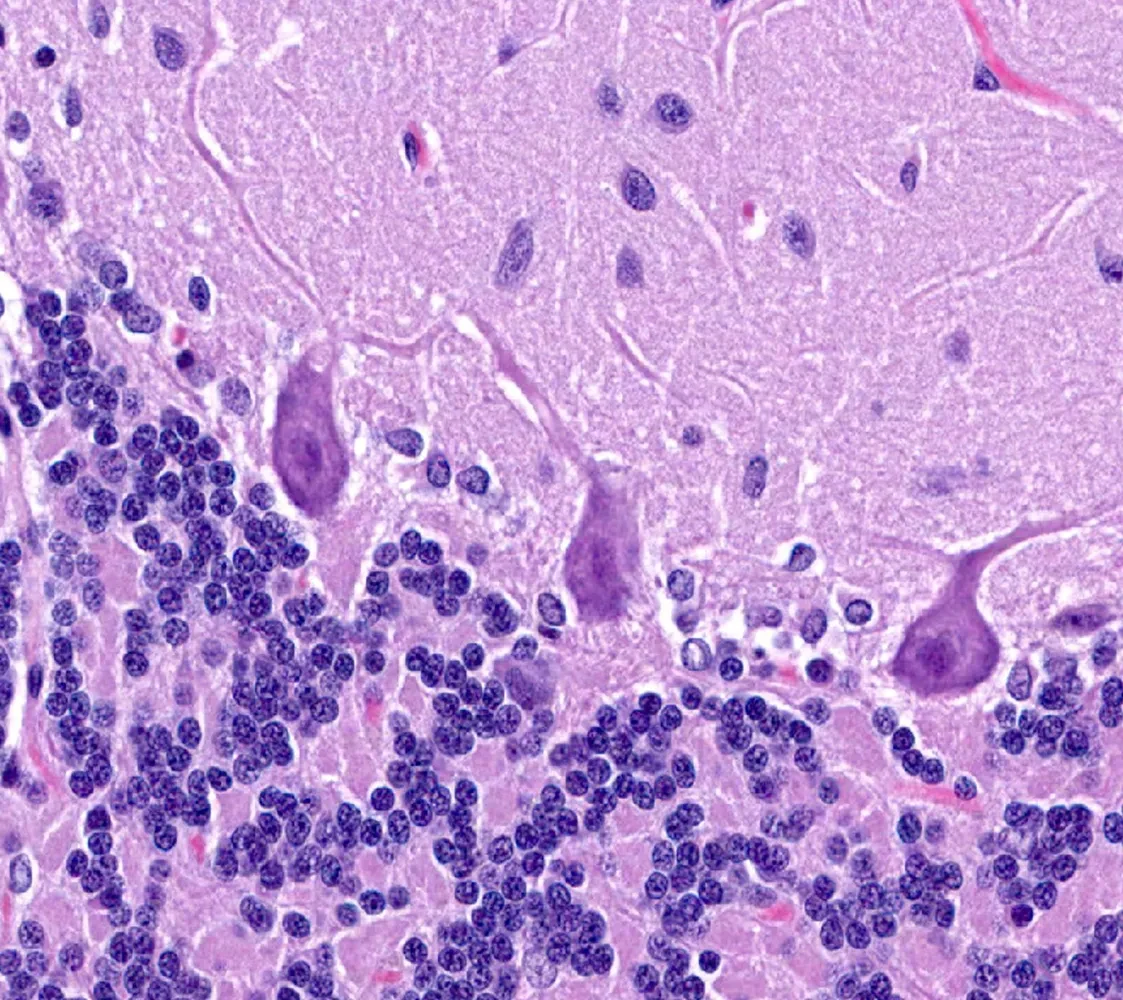

AHC results from an ion imbalance in neurons that impairs the normal functioning of the nervous system. AHC is most frequently caused by a genetic mutation in the ATP1A3 gene, a gene that codes for a catalytic subunit of a pump protein that maintains the critical electrochemical gradient in neurons in the brain. This protein is known as the “sodium-potassium pump”, or the Na+, K+ ATPase. Approximately 70% of AHC cases are caused by a missense mutation in the coding regions of the ATP1A3 gene. More than 200 disease-causing mutations of the ATP1A3 gene have been identified; these mutations cause AHC as well as twelve other rare neurological disorders.